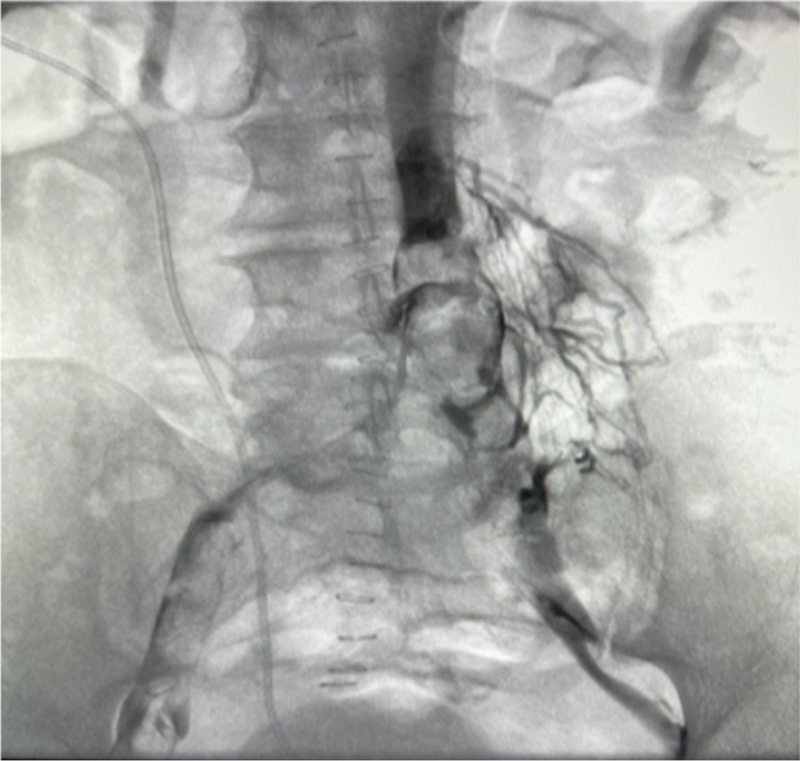

During the mechanical thrombectomy, the patient was placed in the prone position. Bilateral popliteal veins were accessed under ultrasound. Venogram confirmed extensive thrombus in the right and left iliac veins, as well as in the IVC (Figures 1 and 2). Due to IVC involvement, extra-large discs were deployed from the left popliteal vein and above the IVC thrombus for embolic protection. A 13Fr clot retrieving device was inserted on the right. Six passes were made with the clot retriever basket, removing all available IVC and right sided thromboses, which were sub-acute and chronic (Figure 3). The 13Fr clot retriever sheath was then moved to the left popliteal, where five passes were made removing the left-sided thrombi, which also were found to be extremely compacted and likely chronic (Figure 4). The complete thromboses removed are pictured in Figure 5. The patient then received bilateral stents and flow was restored. The patient was discharged two days later on anticoagulation with significant improvement of the lower extremity and pelvic edema.

Figure 3

Figure 3. Post right external iliac vein and IVC thrombectomy.